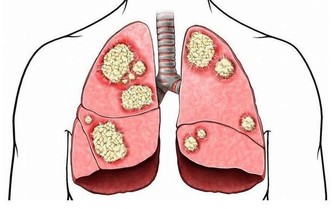

有些胃癌患者,常有伴胃癌綜合徵,如反復發作性血栓性靜脈炎、黑棘皮病、皮膚皺褶有色素沉著、皮肌炎等。